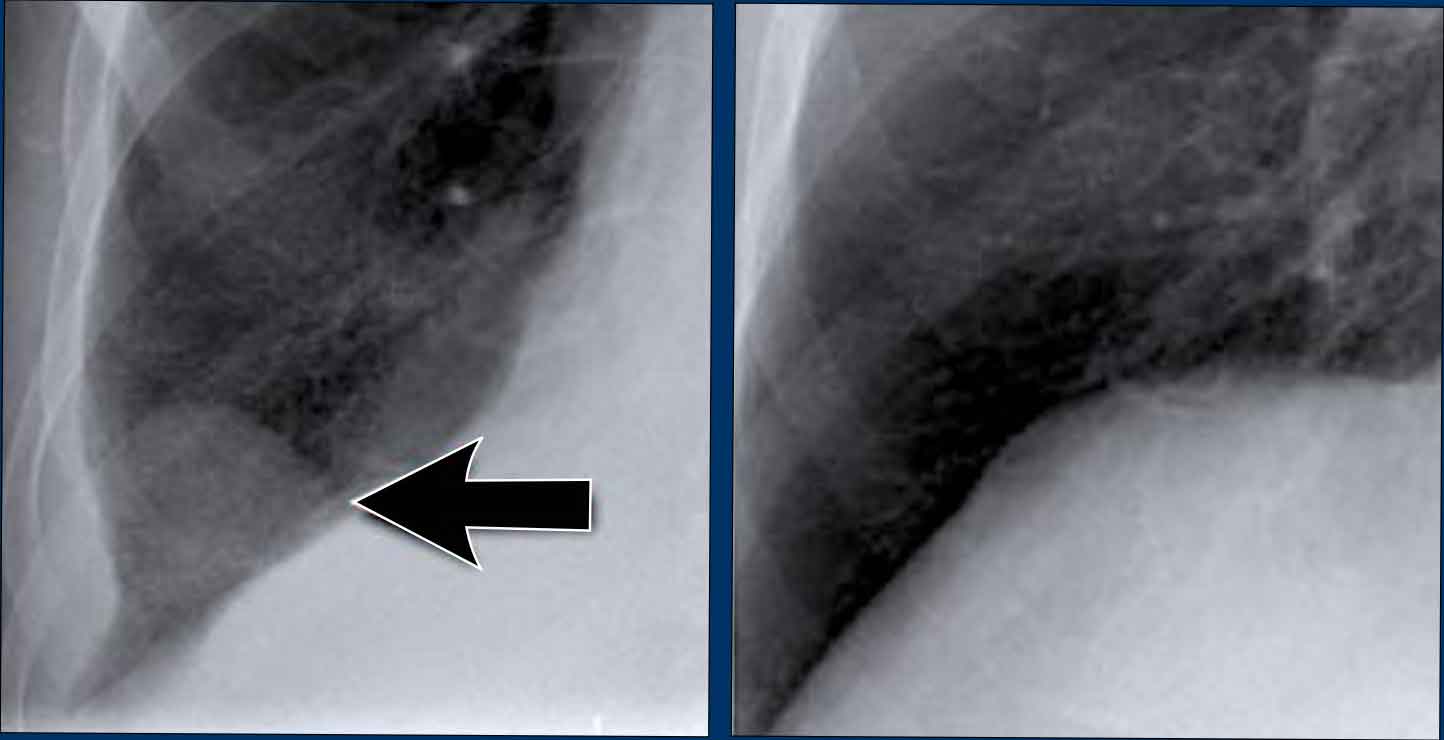

Silhouette Sign – Examples

Case 1: PA View

• The left heart border is obscured on the PA radiograph.

• Without even reviewing the lateral view, this finding localizes the pathology to the anterior segment of the left lung, likely the lingula.

• Diagnosis: Lobar pneumonia due to Streptococcus pneumoniae.

Case 2: PA View

• A consolidation is visible in the left lower lobe (yellow arrow).

• The left heart border remains well-defined with a normal silhouette (blue arrow), indicating the lesion is posterior, not involving the lingula.